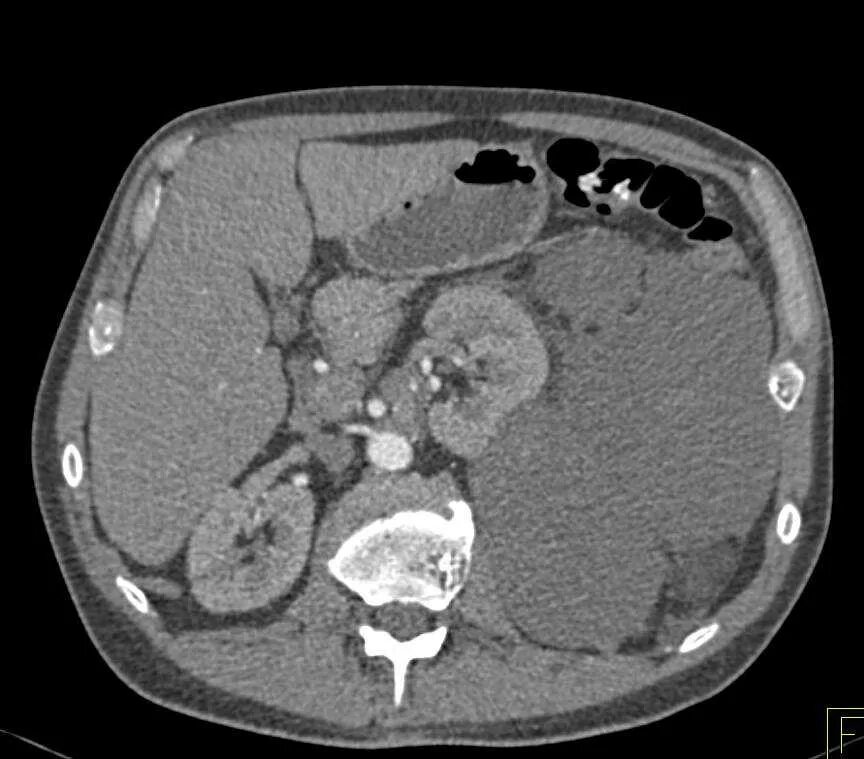

Метастазы при лимфоме